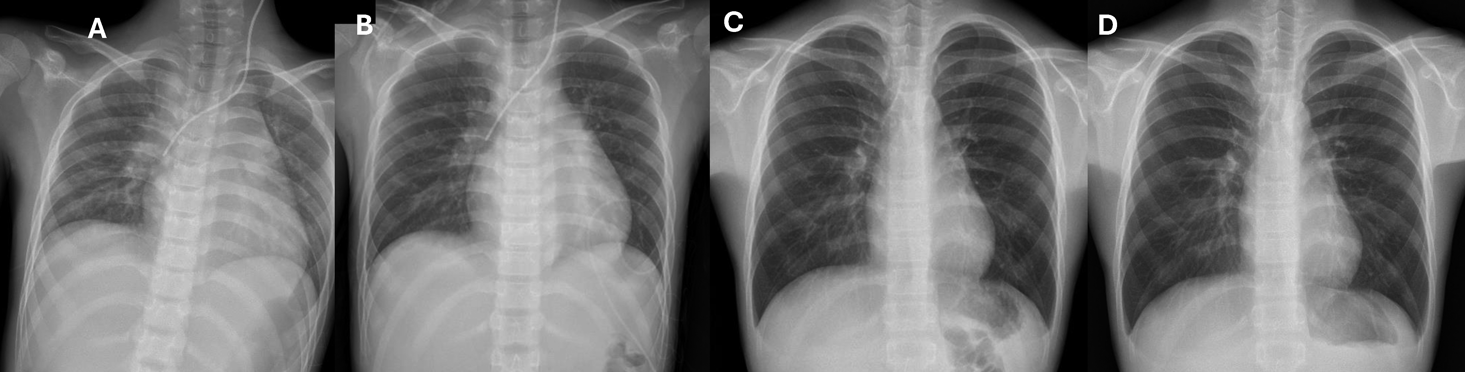

入院時の血液検査で代謝性アシドーシスを認めた.D-dimerは10.2 µg/mLと高値,CK-MBは3.0 ng/dLと軽度高値,トロポニンIは299 pg/mLで高値,BNPは374 pg/mLに上昇していた.ASO,リウマチ因子,甲状腺刺激ホルモンに異常を認めなかった.感染症検査として,多項目ポリメラーゼ連鎖反応(polymerase chain reaction: PCR)パネル検査を行ったがいずれも陰性だった.βDグルカンや結核菌特異的インターフェロンγ検査は陰性,その他提出していた血液学的検査で,CoxA2-IgG抗体と,CoxA9-IgG抗体が32倍(NT法)と後日判明した.胸部X線写真では心胸郭比(cardiothoracic ratio: CTR)59%と心拡大および肺うっ血像を認めた(Fig. 1A).心電図検査では,VSD術後から認めていた完全右脚ブロック波形を認め,全体的にやや低電位だったが,過去の心電図と比較してST部分の変化は認めなかった(Fig. 1B).心臓超音波検査では心臓前面に4 cm程度の心嚢水貯留を認め,右室は圧排されていた(Fig. 1C, D).

Fig. 1 入院時画像所見

A:胸部X線写真半坐位撮像.59%と心拡大を認め,肺うっ血像を認めた.B:心電図.術後より完全右脚ブロックを認めていた.過去と比較して明らかなST変化を認めなかった.C:心臓超音波検査左室短軸像.右室の前面に3 cm程度の心嚢水貯留を認めた.D:心臓超音波検査四腔断面像.心尖部に3 cm程度の心嚢水貯留を認めた.LA:左心房,LV:左心室,PE:心嚢水,RV:右心室.

Fig. 3 レントゲン写真の経時変化

A:入院日,B:入院2日目,C:入院4日目,D:入院7日目.